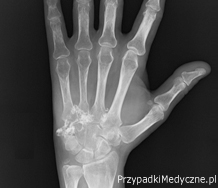

Chrzęstniakomięsak kości nadgarstka - opis przypadku

Chondrosarcoma of bones of wrist - a case report

Surgery

Sitarska M., Czarnecki R., Kokoszka L.

Chondrosarcoma is a malignant neoplasm of the bone. It is the second most common among sarcomas of bones in adults. The early symptom is pain; in later stages, there is a tumor and distortion of the outline of the limb. The first and primary examination is a review roentgenography (X-ray) of the entire bone in two projections along with the adjacent joint. The histopathological diagnosis is established on the basis of an examination of the of tissue material taken during surgical biopsy. Treatment consists of resection of the tumor.